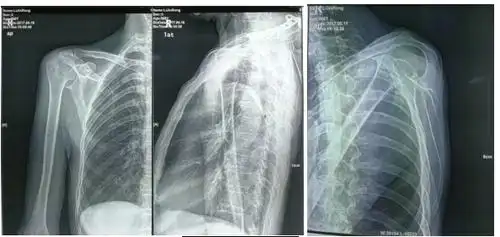

胸部影像挑战# 年轻女性肩痛 1 月,咳嗽 4 天,入院体温 39.9°c.

右肩关节间隙,肩峰下滑囊,喙突下滑囊少量积液.

中年女性,发现右肩关节占位2天.有特征,有细节---(有结果)